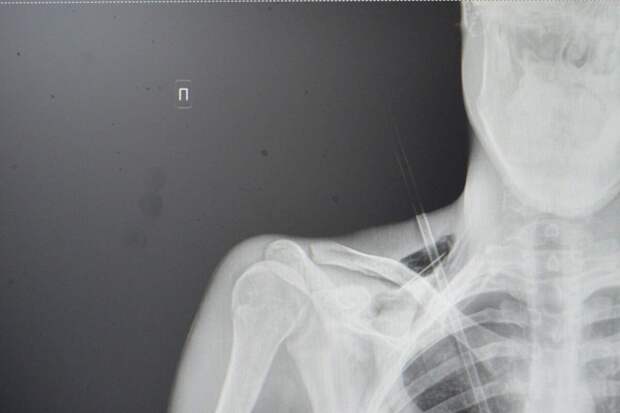

Как рассказали медики, юноша поступил в больницу на скорой со стрелой в грудной клетке. Он рассказал, что вместе с девушкой занимался стрельбой из спортивного лука, когда стрела срикошетила от дерева и вонзилась ему в грудь.

После госпитализации пациента отправили на экстренную операцию: стрела прошла между ключицей и правым ребром, пробив верхушку легкого на шесть сантиметров. По словам врачей, юноше повезло, что предмет не задел подключичную артерию или вену.

"Это привело бы к критическому кровотечению. Такие травмы требуют немедленного хирургического вмешательства. Мы успешно удалили инородное тело, а потом ушили поврежденное легкое и дренировали плевральную полость", - рассказал хирург больницы Тимур Колесников.